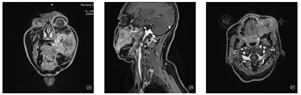

手术情况(包括肿瘤切除、颈清及皮瓣制取):于2020年8月30日在全麻下行:颊颌颈联合根治术+左部分眶内容物摘除术+右股前外侧游离皮瓣修复术(皮瓣大小28 cm×11 cm)+气管切开术。手术切除范围包括:左眼球及其周围附丽组织,部分眶骨,上颌骨,颧骨,部分颧弓,半侧下颌骨,原手术移植的皮瓣,腮腺,部分鼻甲,部分上下唇组织。

皮瓣制取:制取右侧游离股前外皮瓣,考虑组织缺损较大,本次手术切取皮岛大小28 cm×11 cm(术前根据面部切除范围做好切除范围模板,预估手术需要量),完整切取一条股外侧肌及一条股直肌(图4)。2条皮穿支位于皮岛三等分中点,进入股外侧肌均汇入旋股外动脉降支,2条肌穿支位于股直肌中端及近端均汇入旋股外动脉降支,继续向上分离直至所有分支动静脉汇合至一支动脉干和一支静脉干,作为断蒂处,同时将周围动静脉分支予以结扎。皮瓣断蒂后,右大腿供区创面借助皮肤牵张闭合器拉拢缝合。

微血管吻合情况(图5):左侧既往颈清手术无可用血管,右颈淋巴清扫术后发现:静脉受区:颈内静脉仅一支分支可供使用,动脉受区:仅甲状腺上动脉一支分支可供使用。受、供区动静脉血管管径基本匹配(3.5 mm/4.0 mm),供区动脉血管管径过大(约4.0 mm),受区动脉血管管径过小(约2.0 mm)。静脉端端使用4.0 mm微血管吻合器进行吻合。动脉端端使用9-0滑线,剪开甲状腺上动脉管径进行缝合。吻合后静脉回血通畅,皮瓣皮缘出血,皮瓣血运恢复。

修复重建情况:血管蒂从左侧沿颏下走行至对侧颌下区,将血管蒂摆顺并将血管蒂的周围肌袖与颏部肌肉进行缝合固定,避免血管蒂发生扭转。优先缝合口内侧,1皮穿支位于中心处,直至口角,然后将皮岛进行完全离断,股直肌及股外侧肌完全填塞面部创腔,剩余皮岛(含1皮穿支)与面部皮肤严密缝合,完成口腔及颌面部缺损重建(图6)。

术后皮瓣存活良好,伤口一期愈合,未出现伤口及肺部等感染,右大腿供区伤口愈合良好。

预后评估:现患者进食,语音,吞咽功能良好,患者对治疗效果十分满意。患者左眶内容物摘除,右眼观物,外出社交佩戴墨镜(图7)。